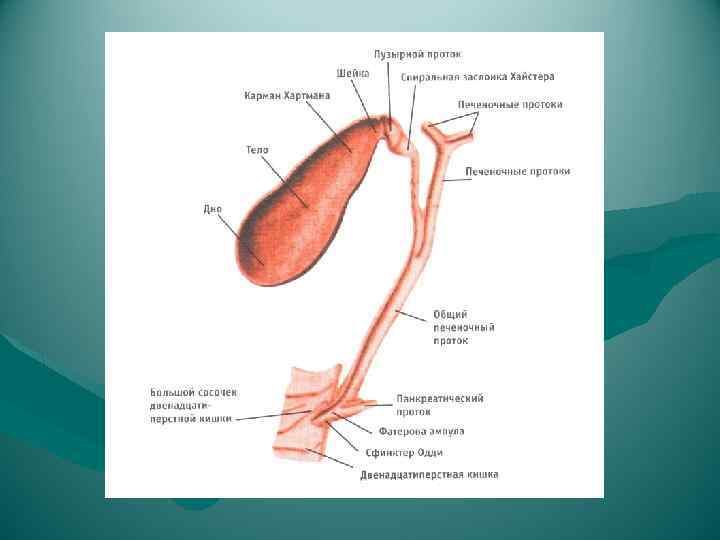

Варианты слияния протоков

Варианты слияния протоков